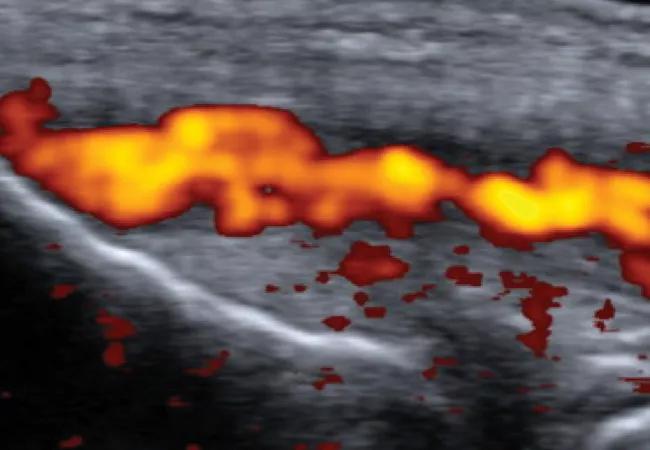

• Hyperemia. Increased color power doppler (CPD) signal within the tendon

We constructed a new classification system based on these MSK-US identified features, and organized them into four distinct pathologic types (Figure 1).